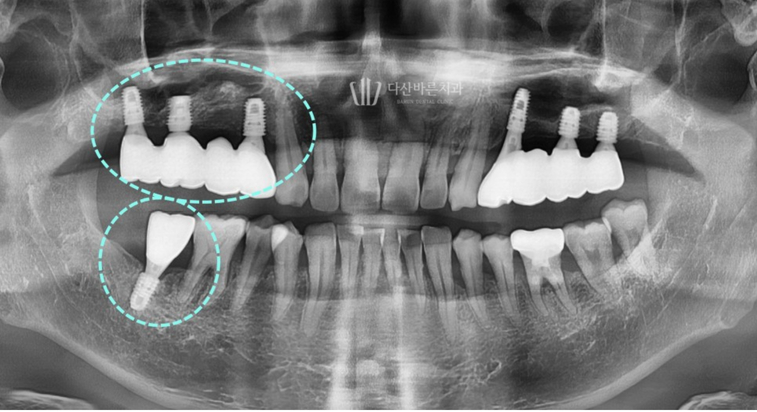

Bệnh nhân này đến bệnh viện với tình trạng

mất răng hàm trên và răng phải đã lâu.

Thoạt nhìn, bệnh nhân đã mất quá nhiều xương nướu để có thể

cấy ghép implant nhưng đã chụp CT 3D để chẩn đoán chính xác hơn độ dày và mật độ xương.

Vì răng đã mất lâu ngày và xương hàm bị mất nhiều

nên cần phải trồng răng implant ghép xương.

Sau khi ghép xương, vị trí và góc đặt implant được lên kế hoạch thông qua quy trình mô phỏng.

Ảnh trên là ảnh chụp quá trình cấy ghép implant mô phỏng.

Với bức ảnh này, bạn có thể kiểm tra trước độ dày của xương

có đủ hay không khi trụ implant (vít, vật cố định) nằm bên trong xương nướu,

sau đó đặt trụ implant ở vị trí và góc chính xác hơn.